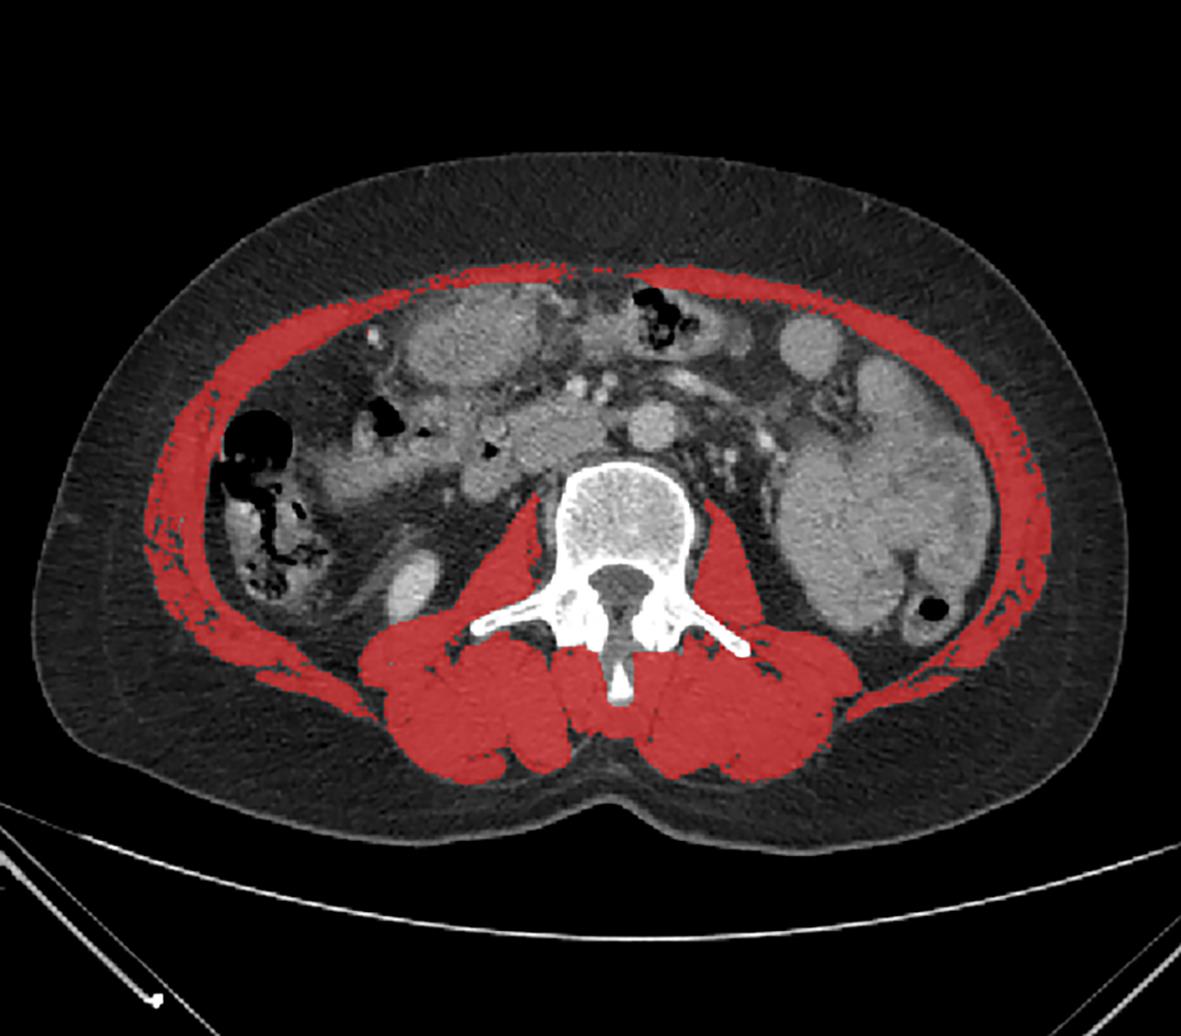

Clinical features of bone mass loss in liver cirrhosis and its association with sarcopenia

Qiu JIN, Jing YANG, Honglin MA, Zhenghao SUN, Qingqing LIU, Shaoshan HU, Pingju LI

2023, 39(12): 2831-2838. DOI: 10.3969/j.issn.1001-5256.2023.12.013

Abstract(1009) HTML (293) PDF (750KB)(95)

Abstract:

Objective  To investigate the influence of sarcopenia on bone mass loss, the risk factors for bone mass loss in liver cirrhosis, and the correlation between body composition and bone mineral density (BMD) by comparing the clinical features of bone mass loss in patients with liver cirrhosis.  Methods  A total of 92 patients who were hospitalized and diagnosed with liver cirrhosis in Department of Gastroenterology, The Second Affiliated Hospital of Kunming Medical University, from April to December of 2022 were enrolled, and based on the results of dual-energy X-ray absorptiometry, they were divided into bone mass loss group (osteopenia/osteoporosis) with 57 patients and normal bone mass group with 35 patients. The two groups were compared in terms of general data, laboratory examination, imaging data, and body composition analysis. The independent samples t-test or the Mann-Whitney U test was used for comparison of continuous data between two groups, and the chi-square test or the continuity correction chi-square test was used for comparison of categorical data between two groups; Pearson correlation analysis and Spearman correlation analysis were used to investigate correlation; a binary logistic regression analysis was used to investigate the risk factors for bone mass loss in liver cirrhosis.  Results  Compared with the normal bone mass group, the bone mass loss group had significantly higher age (t=-3.597, P<0.05), proportion of female patients (χ2=8.393, P<0.05), N-terminal middle molecular fragment of osteocalcin (N-MID) (Z=-3.068, P<0.05), β isomer of C-terminal telopeptide of type I collagen (β-CTX) (t=-2.784, P<0.05), and proportion of patients with sarcopenia (χ2=13.884, P<0.05) and significantly lower calcitonin (CT) (Z=-2.340, P<0.05) and L3 skeletal muscle index (L3-SMI) (t=4.621, P<0.05). Compared with the normal bone mass group, the bone mass loss group had significantly lower total muscle mass (Z=-2.952, P<0.05), right upper limb muscle mass (Z=-2.929, P<0.05), left upper limb muscle mass (Z=-2.680, P<0.05), right lower limb muscle mass (Z=-3.366, P<0.05), left lower limb muscle mass (Z=-3.374, P<0.05), presumed bone mass (t=2.842, P<0.05), body water mass (Z=-2.779, P<0.05), basal metabolic rate (BMR) (Z=-3.153, P<0.05), and BMD of L1— L4 and femoral neck (t=9.789, t=10.280, t=10.832, Z=-7.298, t=8.945, all P<0.05). Total muscle mass, muscle mass of trunk and limbs, presumed bone mass, BMR, and body water mass in body component analysis were positively correlated with L1 — L4 BMD and femoral neck BMD (all P<0.05), and fat mass was positively correlated with L1 — L4 BMD (all P<0.05). Sarcopenia (odds ratio [OR]=8.737, 95% confidence interval [CI]: 2.237 — 34.129, P=0.002), age (OR=1.094, 95%CI: 1.019 — 1.175, P=0.013), and N-MID (OR=1.095, 95%CI: 1.019 — 1.176, P=0.014) were independent risk factors for bone mass loss in patients with liver cirrhosis.  Conclusion  Old age, female sex, sarcopenia, elevated N-MID, elevated β-CTX, reduction in CT, low muscle mass, low presumed bone mass, low BMR, and low body water mass are the features of bone mass loss in patients with liver cirrhosis, and sarcopenia, age, and N-MID are independent risk factors for bone mass loss in patients with liver cirrhosis. Detailed assessment of body composition changes can help to identify abnormal BMD in patients with liver cirrhosis.